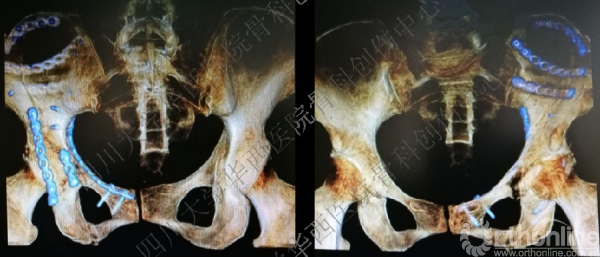

术前三维CT

做三维重建,进一步为手术做术前详细的计划,决定前方入路。

术后三维重建

术后三维重建前面观完美!

术后三维重建后面观,发现后壁的骨折有明显的移位,后脱位的风险增加,我们决定!

CT及三维重建

CT及三维重建也很满意。